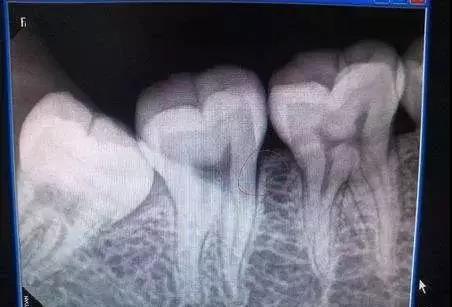

02 牙面有黑点

牙齿表面有黑褐色改变,或有失去光泽的白垩色斑点,或两牙相邻处有变暗的黑晕,这些都是虫牙的早期表现,需尽早治疗,以免牙洞越来越大,伤害到牙神经。